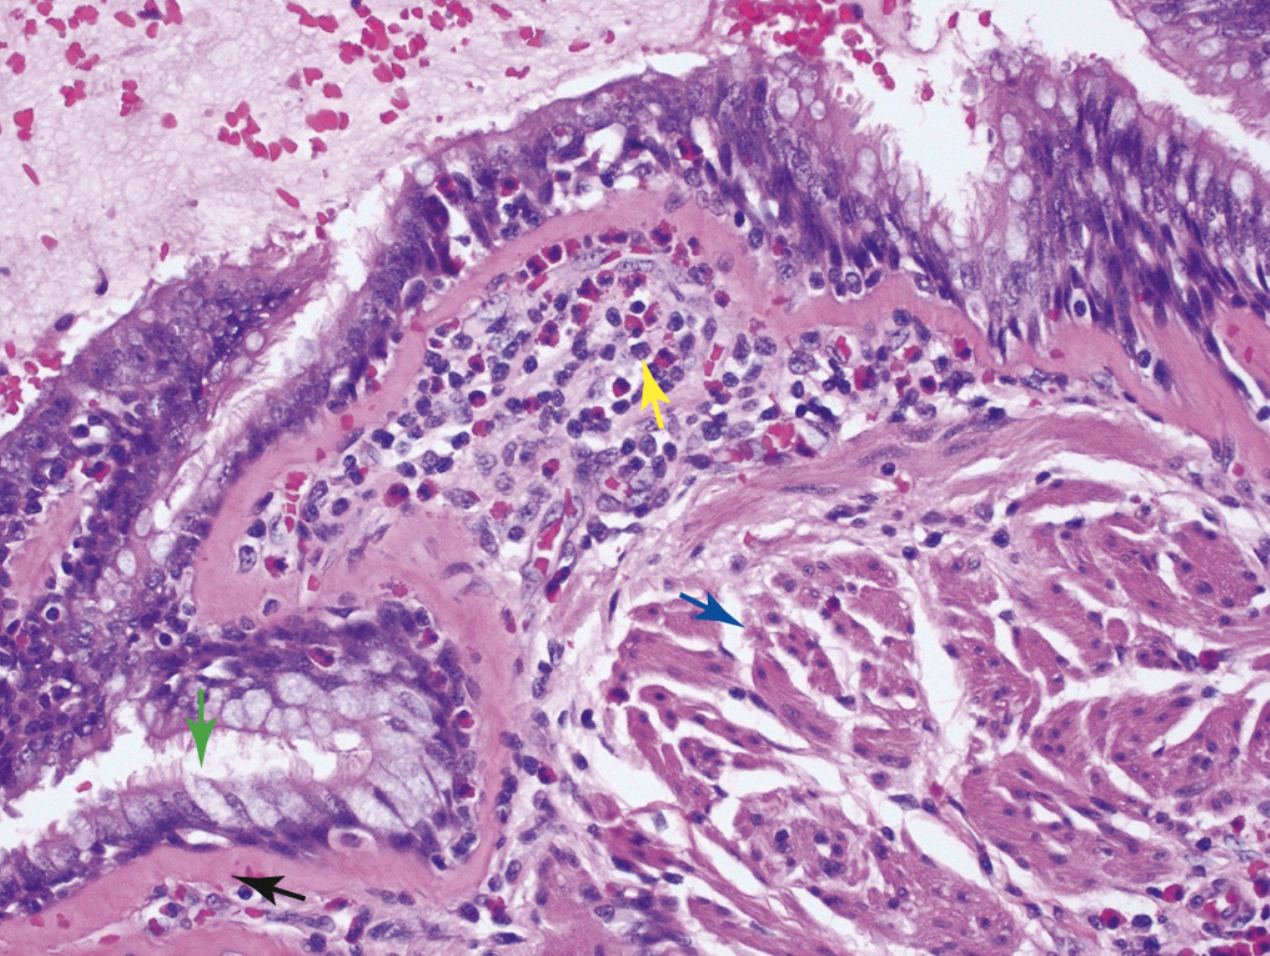

¿Qué está señalando la flecha verde?

Hiperplasia de las células calciformes

¿Qué está señalando la flecha azul?

Hipertrofia muscular

¿Qué está señalando la flecha negra?

Fibrosis subyacente a la membrana basal

¿Qué está señalando la flecha amarilla?

Inflamación eosinofílica